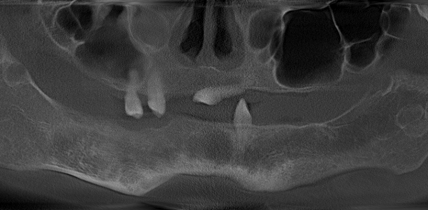

Киянка Ольга Мацик у свої 32 роки мала лише 3 зуби. Причиною цього було надзвичайно рідкісне захворювання – херувізм. За всю історію спостережень у світі фахівці зафіксували близько 300 людей. Задокументовані та описані у літературі випадки зубної імплантації у таких людей — одиниці.

• Херувізм – це рідкісне генетичне захворювання фіброзної та кісткової тканин, яке характеризується збільшенням нижньої та верхньої щелеп, часто пов’язане із втратою зубів та порушенням функції щелеп. Медикаментозна терапія для таких пацієнтів не дає жодних результатів, тому зараз однозначного плану лікування таких хворих не існує. Водночас відсутність зубів може призвести до порушення функцій дихання і ковтання, не кажучи про естетичні вади зовнішності і викликані ними комплекси і депресії.

Дівчина втратила зуби ще у підлітковому віці

"У нас є велика мета — встановити Ользі такі штучні зуби, які б нічим не відрізнялися від справжніх зубів, — каже лікар-стоматолог, Ярослав Заблоцький. — Щоб вона могла їсти, посміхатися і насолоджуватися життям, як звичайна людина зі здоровими зубами Ольга потрапила до нас у клініку, маючи один зуб на нижній щелепі і два зуби на верхній.Випадок настільки складний, що традиційні вставні зубні протези не допоможуть — їм просто нема на чому триматися.Єдиним варіантом є вживлення імплантатів (штучного титанового коріння), до яких прикручуються зубні протези Під час цієї 7-годинної операції, що проводиться під наркозом, лікарі нашої клініки встановили п’ять імплантатів на нижню щелепу і п’ять – на верхню, що було дуже складно та ризиковано, адже через хворобу в кістках щелеп є непрогнозовано порожнечі, що перебудовуються – тому моделювати зубний ряд довелося за допомогою спеціальної комп’ютерної програми".

Попри великі ризики та складність медичного випадку, операція пройшла успішно, але стоматологи не мають 100% впевненості, що імплантати приживуться. Якщо приживка пройде добре, пацієнтці тимчасові зуби замінять постійними вже через 6 місяців.